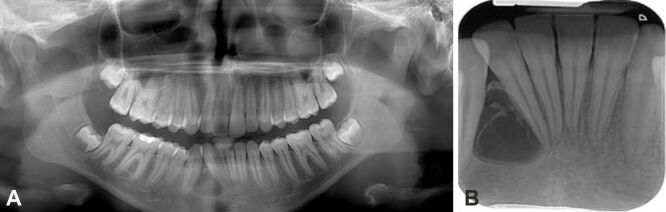

平堡瘤是一种钙化上皮性牙源性肿瘤,可能是由于牙齿薄层残留物的发育障碍引起的。这种肿瘤主要影响生命中第三个十年的人,女性发病较晚。该肿瘤有两种形式,即骨内(中央型)和骨外(周围型),前者的术后复发率较高,约为 14%。尽管这种肿瘤很罕见,但由于其症状类似牙科问题和头痛,甚至可能没有症状,因此可能会被误诊。在放射学上,它表现为放射线透明区和放射线不透明区的混合,有时为单眼或多眼。组织病理学上,它的特征是多角形上皮细胞的巢状和片状,胞质嗜酸性,核仁突出。嗜酸性淀粉样物质和钙化是该病的显著特征,从小凝块到较大的聚集体都有。淀粉样蛋白的确切来源尚不清楚,但认为它们来自降解的角蛋白丝。治疗方法因肿瘤位置而异,由于颌骨肿瘤具有侵袭性生长和对周围组织的侵袭,因此需要进行包括骨切除在内的侵入性手术。准确的个体化治疗对患者的预后至关重要,尤其是在肿瘤钙化缺失的情况下,预示着对健康的严重影响。我们的研究包括一例 12 岁患者的病例报告,该患者到牙科诊所就诊时主诉右下门牙部位零星疼痛。在对该区域进行临床检查时,我们发现牙槽骨变形,粘膜凹陷。我们按照放射学检查、病灶切除和组织病理学检查的时间顺序进行了检查,以获得明确诊断。

Pindborg tumor is a calcifying epithelial odontogenic tumor possibly arising from developmental disturbances in dental lamina remnants. It predominantly affects individuals in their third decade of life, with women also experiencing later onset. The tumor exists in two forms, namely intraosseous (central) and extraosseous (peripheral), with the former showing higher post-surgery recurrence rates of about 14%. Despite its rarity, the tumor can be misdiagnosed due to symptoms resembling dental issues and headaches, or it may even be asymptomatic. Radiologically, it presents a mix of radiolucent and radiopaque areas, sometimes unilocular or multilocular. Histopathologically, it is characterized by nests and sheets of polygonal epithelial cells with eosinophilic cytoplasm and prominent nucleoli. The presence of eosinophilic amyloid-like material and calcifications is distinctive, ranging from small concretions to larger aggregates. The exact origin of amyloids is unknown, but they are thought to derive from degraded keratin filaments. Treatment varies by tumor location, with more invasive procedures required for jaw tumors, including bone resection, due to their aggressive growth and invasion of the surrounding tissues. Accurate, individualized treatment is crucial for patient outcomes, particularly in cases where the tumor's calcification is absent, indicating a severe impact on health. Our study included a case report of a 12-year-old patient who presented to the dental clinic complaining of sporadic pain in the area of the lower right front teeth. During a clinical examination of the area, we noticed a deformation of the alveolar bone, with a depressed mucosa. We followed the chronological steps of radiological examination, lesion excision, and histopathological examination to obtain a definitive diagnosis.